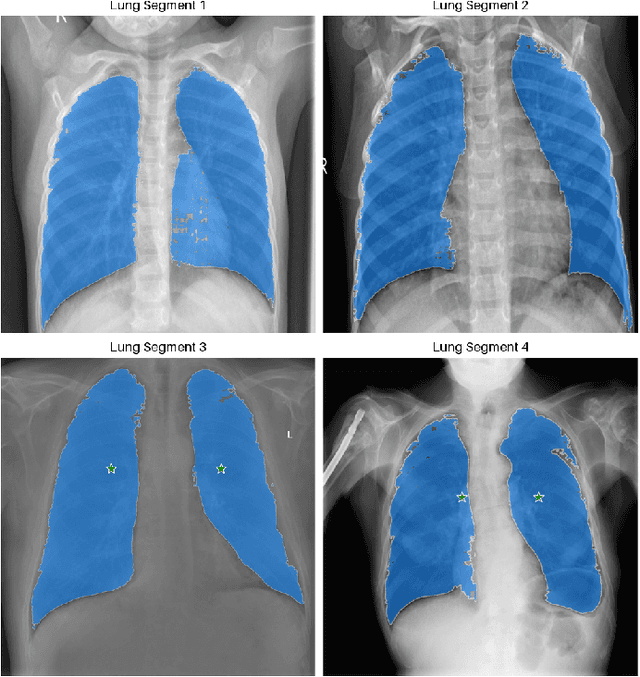

Tuberculosis (TB) is a chronic lung disease that occurs due to bacterial infection and is one of the top 10 leading causes of death. Accurate and early detection of TB is very important, otherwise, it could be life-threatening. In this work, we have detected TB reliably from the chest X-ray images using image pre-processing, data augmentation, image segmentation, and deep-learning classification techniques. Several public databases were used to create a database of 700 TB infected and 3500 normal chest X-ray images for this study. Nine different deep CNNs (ResNet18, ResNet50, ResNet101, ChexNet, InceptionV3, Vgg19, DenseNet201, SqueezeNet, and MobileNet), which were used for transfer learning from their pre-trained initial weights and trained, validated and tested for classifying TB and non-TB normal cases. Three different experiments were carried out in this work: segmentation of X-ray images using two different U-net models, classification using X-ray images, and segmented lung images. The accuracy, precision, sensitivity, F1-score, specificity in the detection of tuberculosis using X-ray images were 97.07 %, 97.34 %, 97.07 %, 97.14 % and 97.36 % respectively. However, segmented lungs for the classification outperformed than whole X-ray image-based classification and accuracy, precision, sensitivity, F1-score, specificity were 99.9 %, 99.91 %, 99.9 %, 99.9 %, and 99.52 % respectively. The paper also used a visualization technique to confirm that CNN learns dominantly from the segmented lung regions results in higher detection accuracy. The proposed method with state-of-the-art performance can be useful in the computer-aided faster diagnosis of tuberculosis.